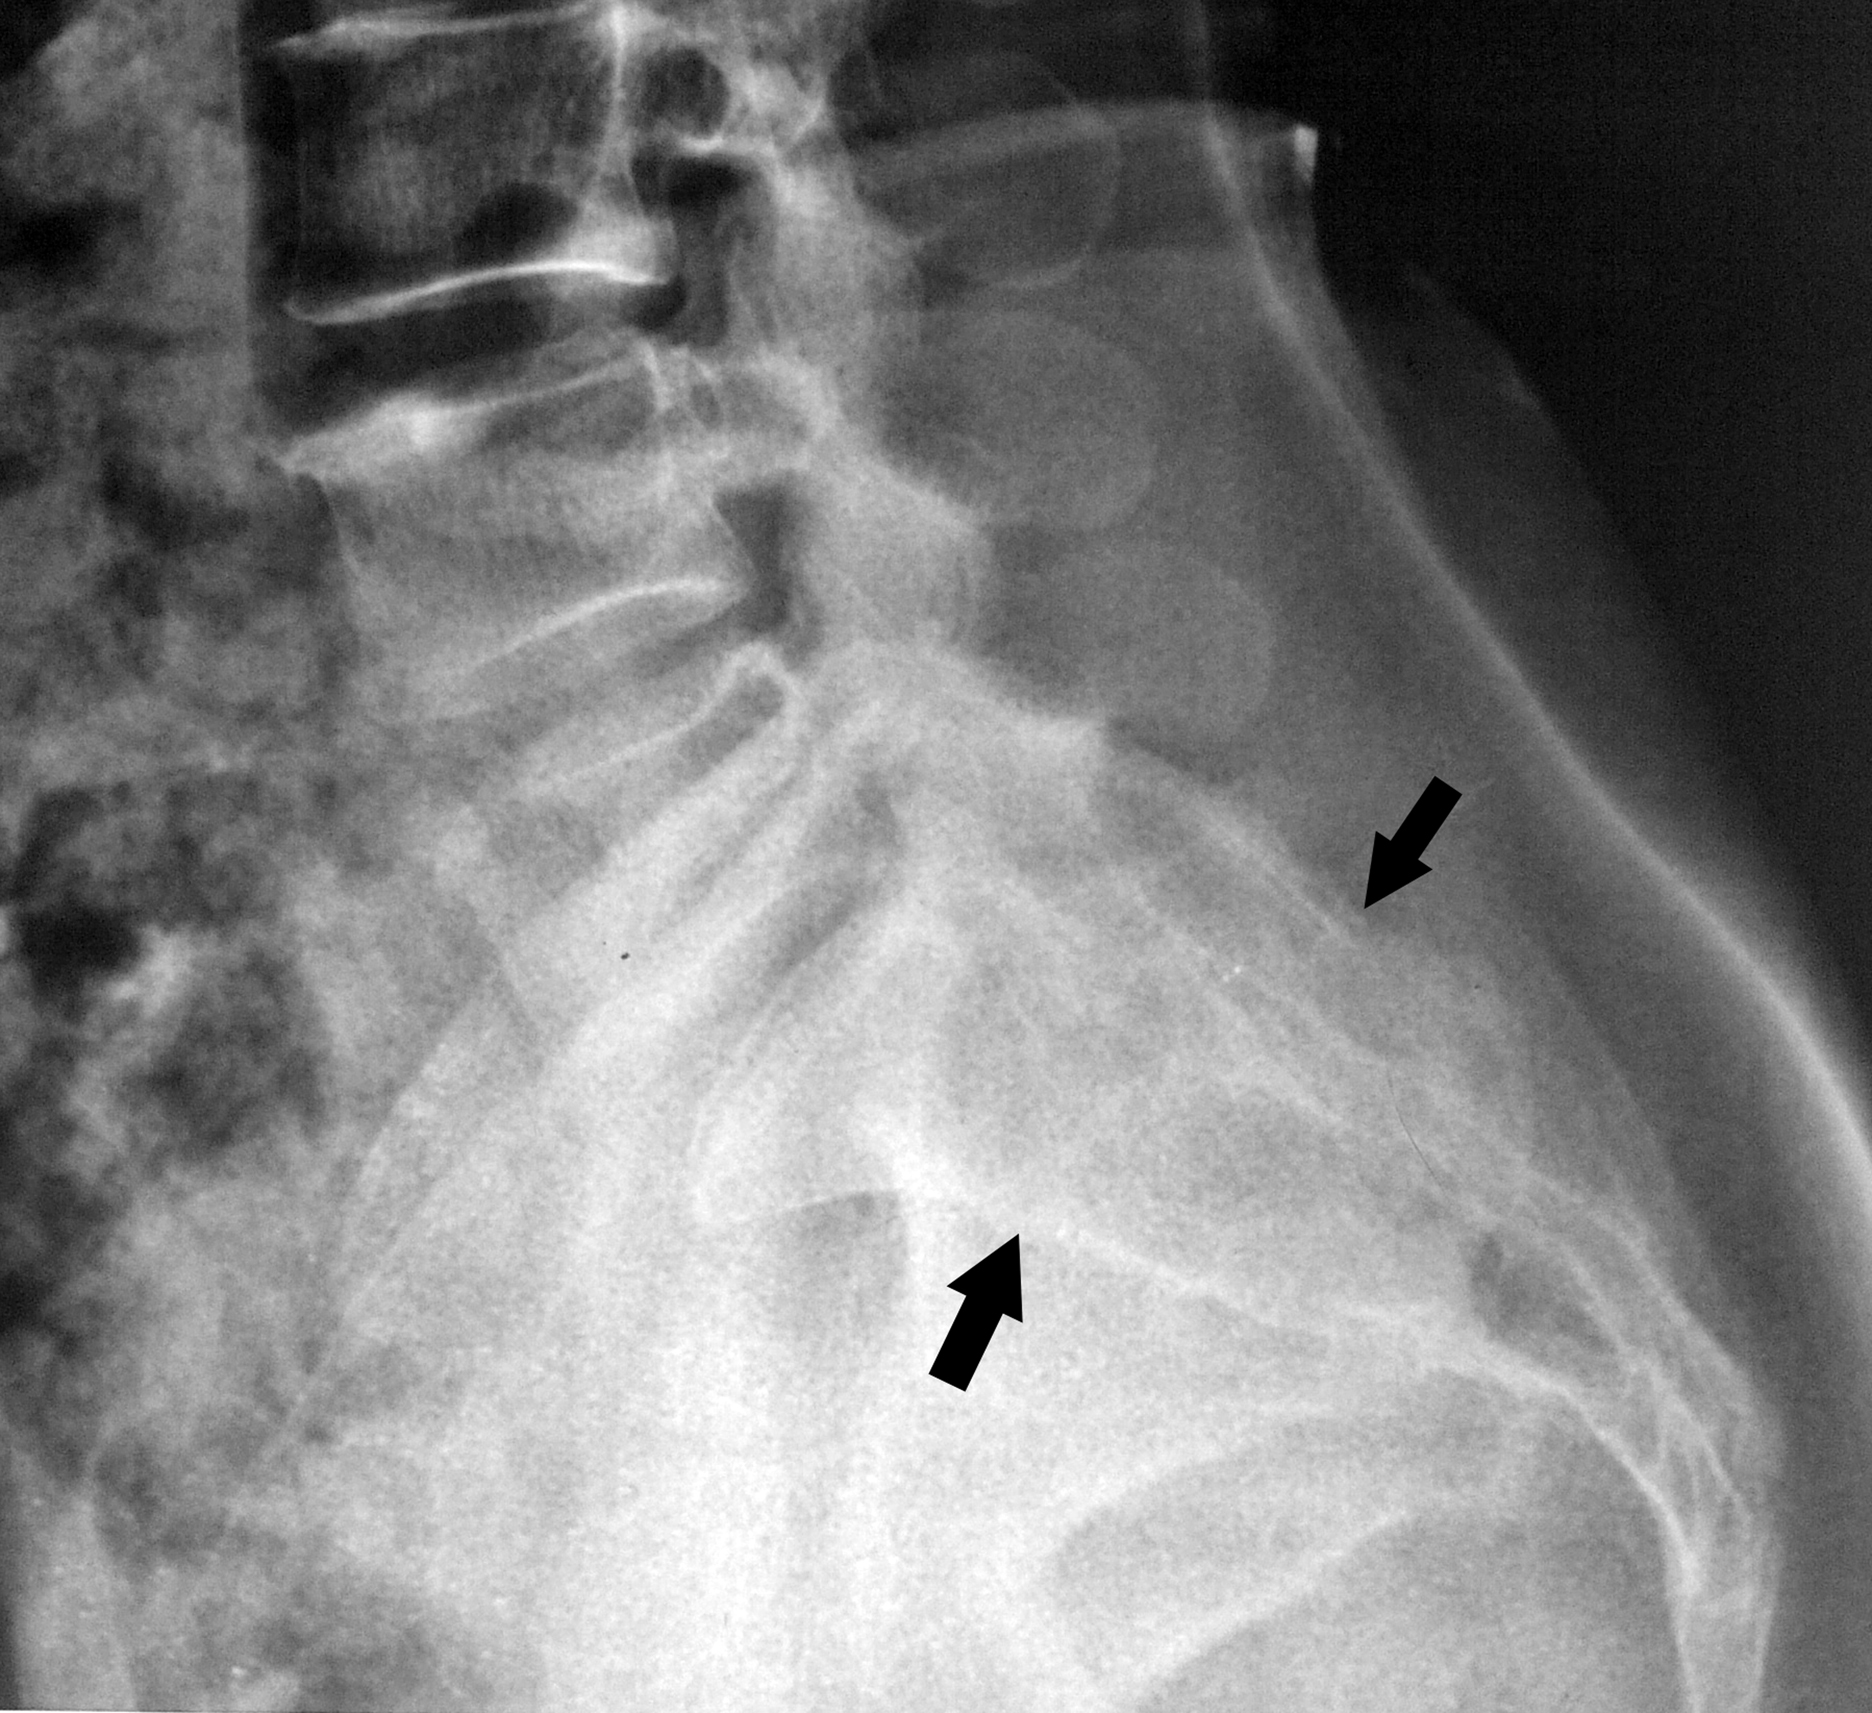

Sacral arachnoid cyst presenting as chronic low back pain

Agrawal, A., Santhi, V., & Rao, G. M. (2014). Sacral arachnoid cyst presenting as chronic low back pain. Bangladesh Journal of Medical Science, 14(1), 106–108. https://doi.org/10.3329/bjms.v14i1.16191